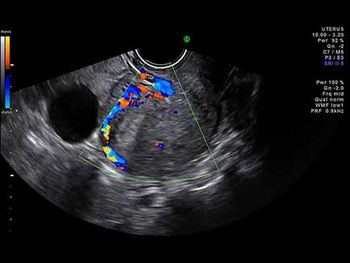

A routine ultrasound exam of a 28-week fetus revealed what looked to be a cystic lesion. The addition of Doppler, however, changed the diagnostic picture.